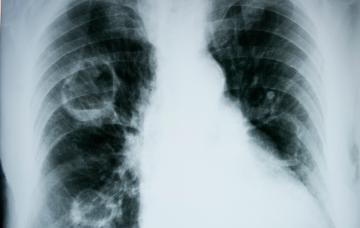

Diagnóstico del edema pulmonar

Los síntomas que presenta el paciente y los antecedentes previos hacen sospechar un diagnóstico de edema pulmonar, que se confirma con estas pruebas.